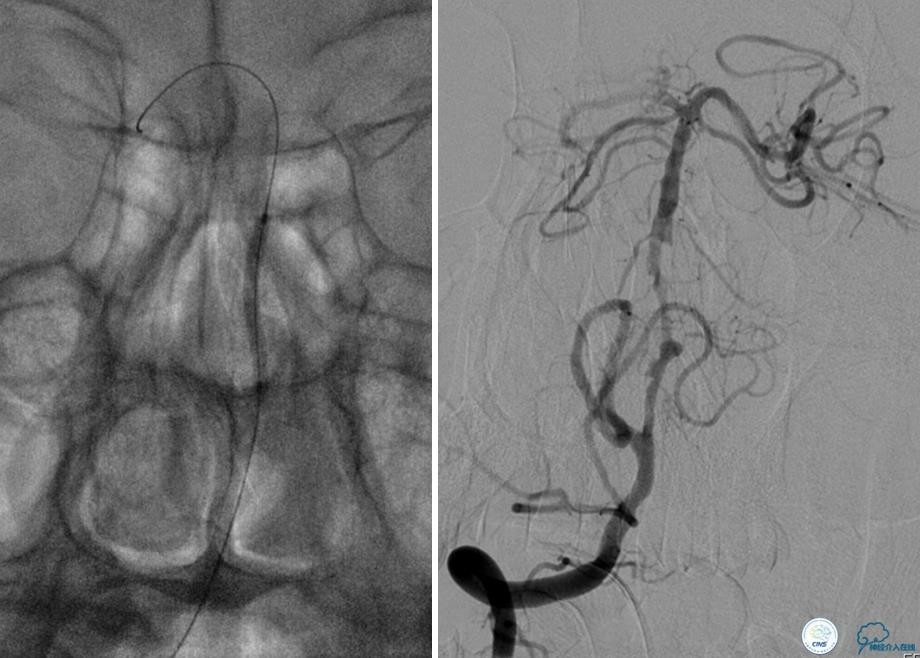

患者:53岁男性,反复脑梗死3个月。

▼给予球囊扩张成形,闭塞段较长,决定药物治疗观察,二期再给予支架治疗。

▼药物治疗1个月,再次发作。再次来我院支架治疗。

▼支架术后,效果好。

因此,某些患者分期治疗也具有合理性。